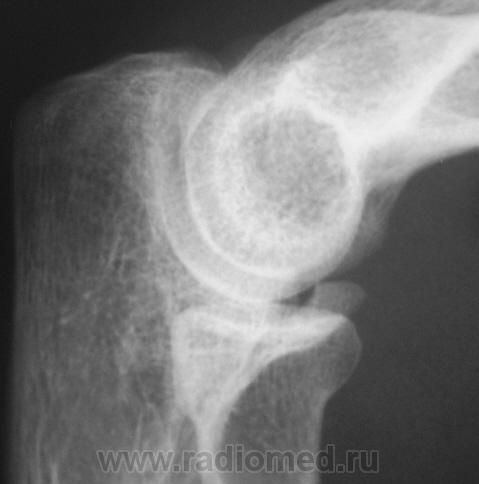

Травма. Пациент направлен на рентгенографию локтевого сустава.

Травма.    Пациент направлен на рентгенографию локтевого сустава. Исследование произведено.